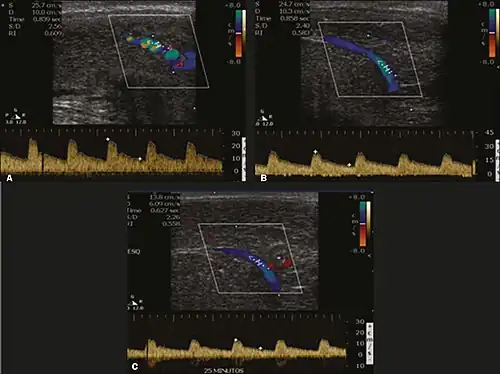

Penile ultrasonography with doppler can be used to examine the erect penis. Most cases of ED of organic causes are related to changes in blood flow in the corpora cavernosa, represented by occlusive artery disease (in which less blood is allowed to enter the penis), most often of atherosclerotic origin, or due to failure of the veno-occlusive mechanism (in which too much blood circulates back out of the penis). Before the Doppler sonogram, the penis should be examined in B mode, in order to identify possible tumors, fibrotic plaques, calcifications, or hematomas, and to evaluate the appearance of the cavernous arteries, which can be tortuous or atheromatous.[48]

Erection can be induced by injecting 10–20 μg of prostaglandin E1, with evaluations of the arterial flow every five minutes for 25–30 min (see image). The use of prostaglandin E1 is contraindicated in patients with predisposition to priapism (e.g., those with sickle cell anemia), anatomical deformity of the penis, or penile implants. Phentolamine (2 mg) is often added. Visual and tactile stimulation produces better results. Some authors recommend the use of sildenafil by mouth to replace the injectable drugs in cases of contraindications, although the efficacy of such medication is controversial.[48]

Before the injection of the chosen drug, the flow pattern is monophasic, with low systolic velocities and an absence of diastolic flow. After injection, systolic and diastolic peak velocities should increase, decreasing progressively with vein occlusion and becoming negative when the penis becomes rigid (see image below). The reference values vary across studies, ranging from > 25 cm/s to > 35 cm/s. Values above 35 cm/s indicate the absence of arterial disease, values below 25 cm/s indicate arterial insufficiency, and values of 25–35 cm/s are indeterminate because they are less specific (see image below). The data obtained should be correlated with the degree of erection observed. If the peak systolic velocities are normal, the final diastolic velocities should be evaluated, those above 5 cm/s being associated with venogenic ED.[48]

Graphs representing the color Doppler spectrum of the flow pattern of the cavernous arteries during the erection phases. A: Single-phase flow with minimal or absent diastole when the penis is flaccid. B: Increased systolic flow and reverse diastole 25 min after injection of prostaglandin.[48] -

Longitudinal, ventral ultrasound of the penis, with pulsed mode and color Doppler. Flow of the cavernous arteries at 5, 15, and 25 min after prostaglandin injection (A, B, and C, respectively). The cavernous artery flow remains below the expected levels (at least 25–35 cm/s), which indicates ED due to arterial insufficiency.[48]